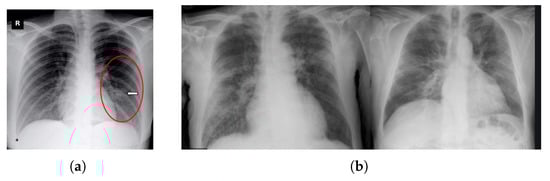

Several studies have shown that the deep learning model trained using chest radiography images has produced better accuracy that can possibly overcome the drawbacks of the RT-PCR technique in the near future. To diagnose and medicate this disease, two types of chest radiological images play a vital role: computed tomography (CT) and X-ray [7]. In comparison to X-rays, CT scans need high radiation in the screening process [8]. In this case, although CT scans provide subtle details, X-ray images are available and patients can easily and rapidly have X-ray images in a more cost-saving way. Additionally, an X-ray generates low ionizing radiations and is the less invasive substitute. Therefore, applying X-ray images in order to train deep learning can create a sustainable COVID-19 detection model and alternative to RT-PCR. Considering the benefits of chest X-ray images, we prefer it to CT scans to conduct the investigation of the proposed model. Figure 1a shows the overview of the COVID-19 situation in the environment including symptoms of this disease, testing process, and identification with a confirmed COVID-19 patient’s sample of chest X-ray images.

Figure 1.

Overview and detection scheme of COVID-19. (a) Overview of COVID-19 state in the environment, symptoms, testing, identification with confirmed COVID-19 patient’s chest X-ray sample. (b) Modified ResNet50V2 for COVID detection where the 1st part is considered as feature extraction part and then the 2nd part is considered as a classification of different cases images, and lastly, the 3rd part is considered as performance and visualization of the X-ray images part.